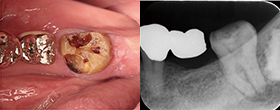

EdgeSequel Sapphire™を使用した臨床例

Case1 湾曲根管

Case2 直線根管